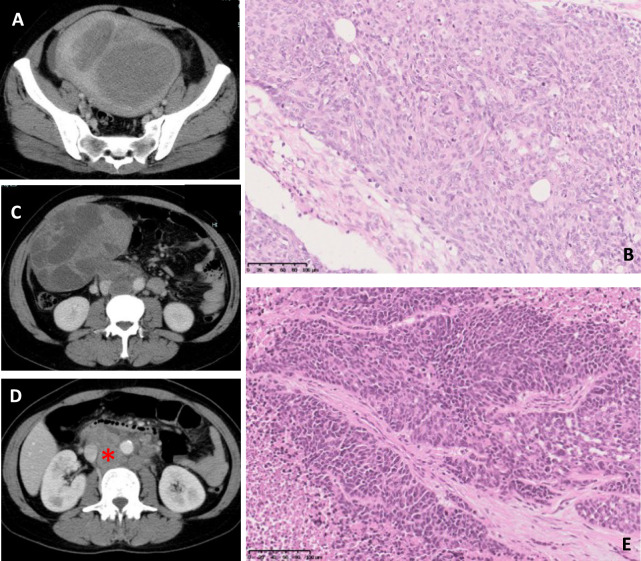

The immune checkpoint system suppresses T-cell activity. Unlike cytotoxic anticancer drugs that directly kill cells, immune checkpoint inhibitors (ICIs) are generally safer by stimulating tumor immunity. However, most clinical trials require patients to have a better performance status (PS), leaving limited evidence for those with poorer PS. In practice, patients may be classified with poor PS due to tumor-induced pain and motor dysfunction, even if major organs remain functional. Real-world data on non-small cell lung cancer has shown no safety difference between patients with PS 3/4 and those with lower PS. Approximately 20-30% of endometrial cancer cases show microsatellite instability-high (MSI-high), the highest among common malignancies. A 46-year-old patient with advanced, recurrent endometrial cancer resistant to standard chemotherapy, and PS of 4 from severe pelvic pain, was diagnosed with MSI-high. Pembrolizumab was initiated and continued for 19 courses, after which lesions had disappeared or calcified, leading to drug discontinuation. Now, 4 and a half years post-treatment, she has regained independent mobility and returned to work, and her PS has improved to approximately 1. Side effects included Grade 2 or lower thyroiditis, hypothyroidism, and hypoadrenalism, manageable with hormone replacement therapy and temporary pembrolizumab suspension. This case underscores the need to test for MSI-high/mismatch repair deficiency in endometrial cancer and to consider ICI therapy in patients with poor PS but no major organ dysfunction. In such cases, ICI can rapidly improve overall condition, a phenomenon known as a Lazarus-type response, as seen in other cancers such as non-small cell lung cancer.